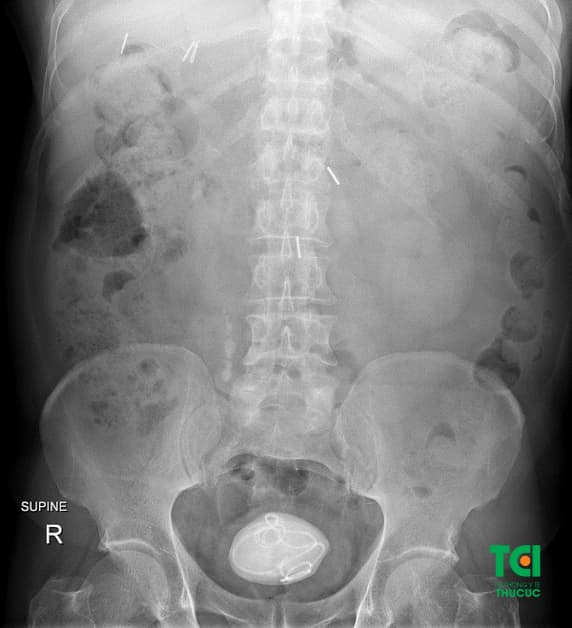

Bệnh nhân mổ sỏi bàng quang tại Thu Cúc TCI